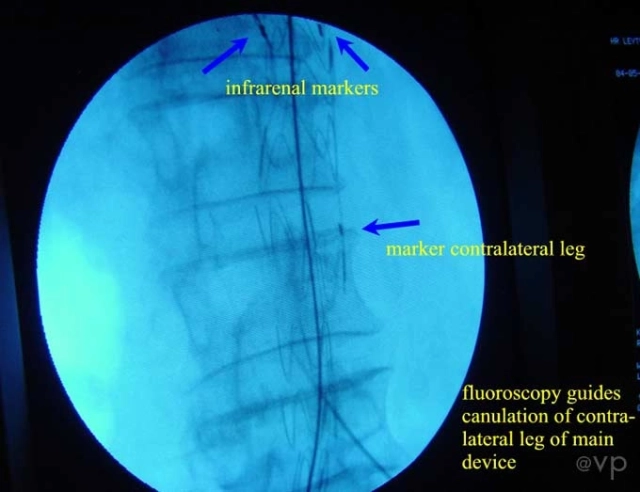

Aortoiliac

| EVAR